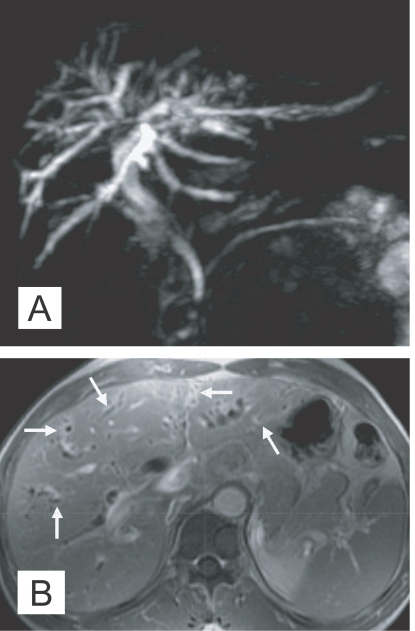

The International Agency for Research on Cancer working group (1994) suggested that C. sinensis is a presumed carcinogen. Now, the relationship between clonorchiasis and cholangiocarcinomas is generally accepted, as epidemiological, pathological and experimental evidences, indicating a positive correlation, have been accumulated (Belamaric, 1973; Shin et al., 1996; Lee et al., 1997; Choi et al., 2006; Lim et al., 2006).

The imaging findings of clonorchiasis-associated cholangiocarcinomas are combinations of the findings of the 2 diseases (Figs. 5 and 6) (Choi et al., 2004). Diffuse dilatation of peripheral intrahepatic ducts is attributed to changes that are secondary to clonorchiasis, and segmental and severe dilatation around the tumor is caused by obstruction by the tumor (Fig. 5) (Choi et al., 1988 & 1989). Extrahepatic cholangiocarcinomas, associated with clonorchiasis, show diffuse dilatation of the peripheral and central intrahepatic bile ducts (Fig. 6). When an extrahepatic cholangiocarcinoma is not associated with clonorchiasis, dilatation of the peripheral intrahepatic bile ducts is not conspicuous (Fig. 7). After the development of the distal obstruction due to an extrahepatic cholangiocarcinoma, pre-existent dilated intrahepatic bile ducts with clonorchiasis easily progress the dilatation.

Fig. 5

Cholangiocarcinoma in the right hepatic lobe, with clonorchiasis, in a 63-year-old man. There is diffuse dilatation of peripheral intrahepatic bile ducts (arrowheads) is attributed to changes of a C. sinensis infection, and segmental and more severe dilatation around the tumor is caused by obstruction by the tumor (arrows).

Fig. 6

Cholangiocarcinoma in the mid common duct, with clonorchiasis, in a 64-year-old man. A. MR cholangiography shows a diffuse dilatation of the intrahepatic bile ducts and common duct. Note an intraluminal tumor (arrows) at the level of the mid common duct. B. Contrast-enhanced CT shows diffuse and marked dilatation of the intrahepatic bile ducts. C. CT at a level lower than (B) shows the enhancing, segmental thickened wall (arrows) of the mid common duct, which represents an extrahepatic cholangiocarcinoma.

Fig. 7

Cholangiocarcinoma in the mid common duct, without clonorchiasis, in a 65-year-old woman. A. MR cholangiography shows an intraluminal tumor (arrows) at the level of the mid common duct. B. Contrast-enhanced CT shows minimal dilatation of the central intrahepatic duct (arrows), but the peripheral intrahepatic ducts are not dilated. C. CT at a level lower than (B) shows the enhancing, segmental thickened wall (arrows) of the mid common duct, which represents an extrahepatic cholangiocarcinoma.

Fig. 5 Cholangiocarcinoma in the right hepatic lobe, with clonorchiasis, in a 63-year-old man. There is diffuse dilatation of peripheral intrahepatic bile ducts (arrowheads) is attributed to changes of a C. sinensis infection, and segmental and more severe dilatation around the tumor is caused by obstruction by the tumor (arrows).

Fig. 6 Cholangiocarcinoma in the mid common duct, with clonorchiasis, in a 64-year-old man. A. MR cholangiography shows a diffuse dilatation of the intrahepatic bile ducts and common duct. Note an intraluminal tumor (arrows) at the level of the mid common duct. B. Contrast-enhanced CT shows diffuse and marked dilatation of the intrahepatic bile ducts. C. CT at a level lower than (B) shows the enhancing, segmental thickened wall (arrows) of the mid common duct, which represents an extrahepatic cholangiocarcinoma.

Fig. 7 Cholangiocarcinoma in the mid common duct, without clonorchiasis, in a 65-year-old woman. A. MR cholangiography shows an intraluminal tumor (arrows) at the level of the mid common duct. B. Contrast-enhanced CT shows minimal dilatation of the central intrahepatic duct (arrows), but the peripheral intrahepatic ducts are not dilated. C. CT at a level lower than (B) shows the enhancing, segmental thickened wall (arrows) of the mid common duct, which represents an extrahepatic cholangiocarcinoma.